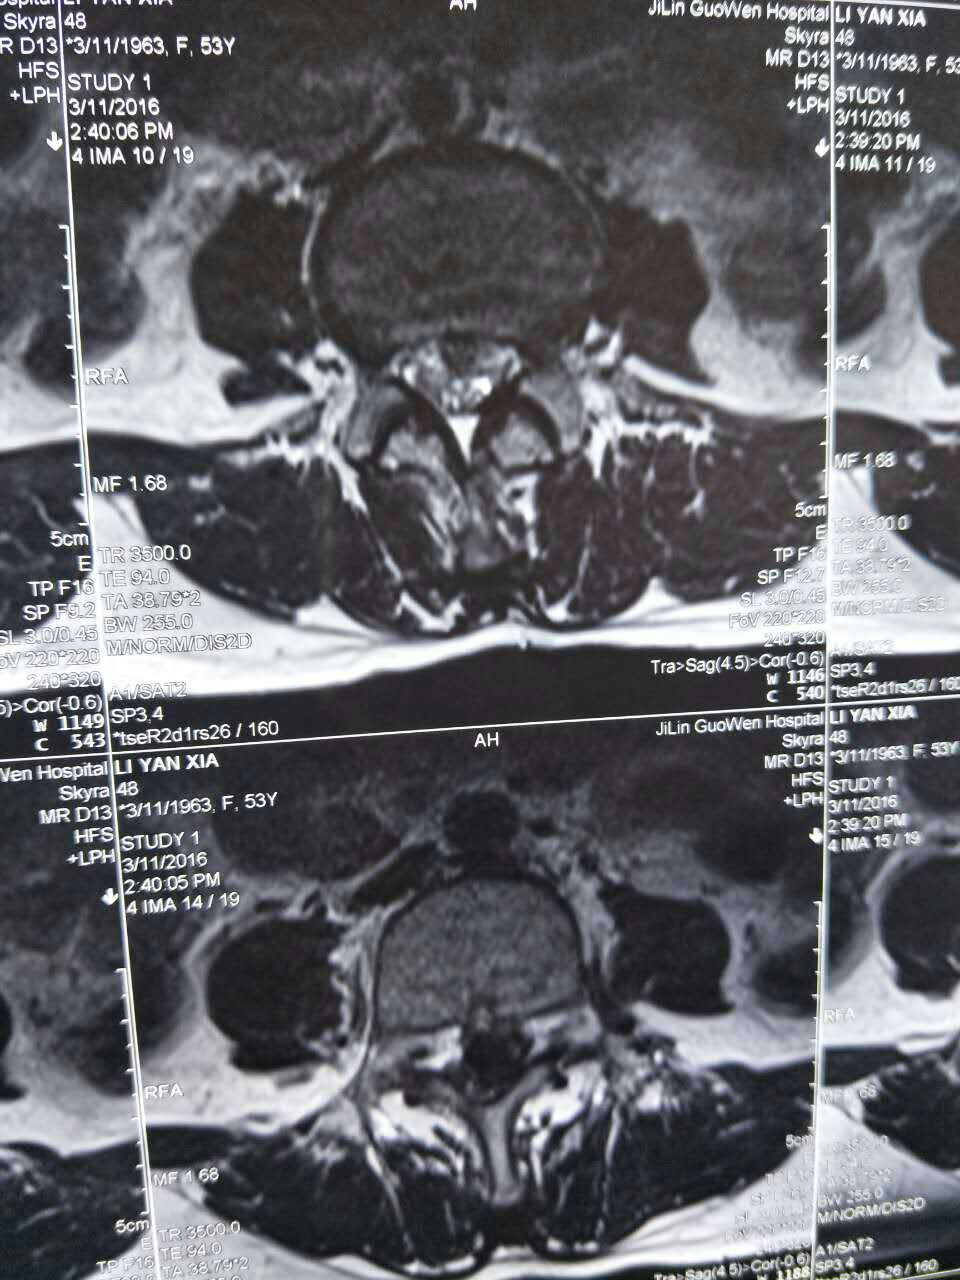

術(shù)前腰椎核磁檢查有助于診斷及確定手術(shù)方案